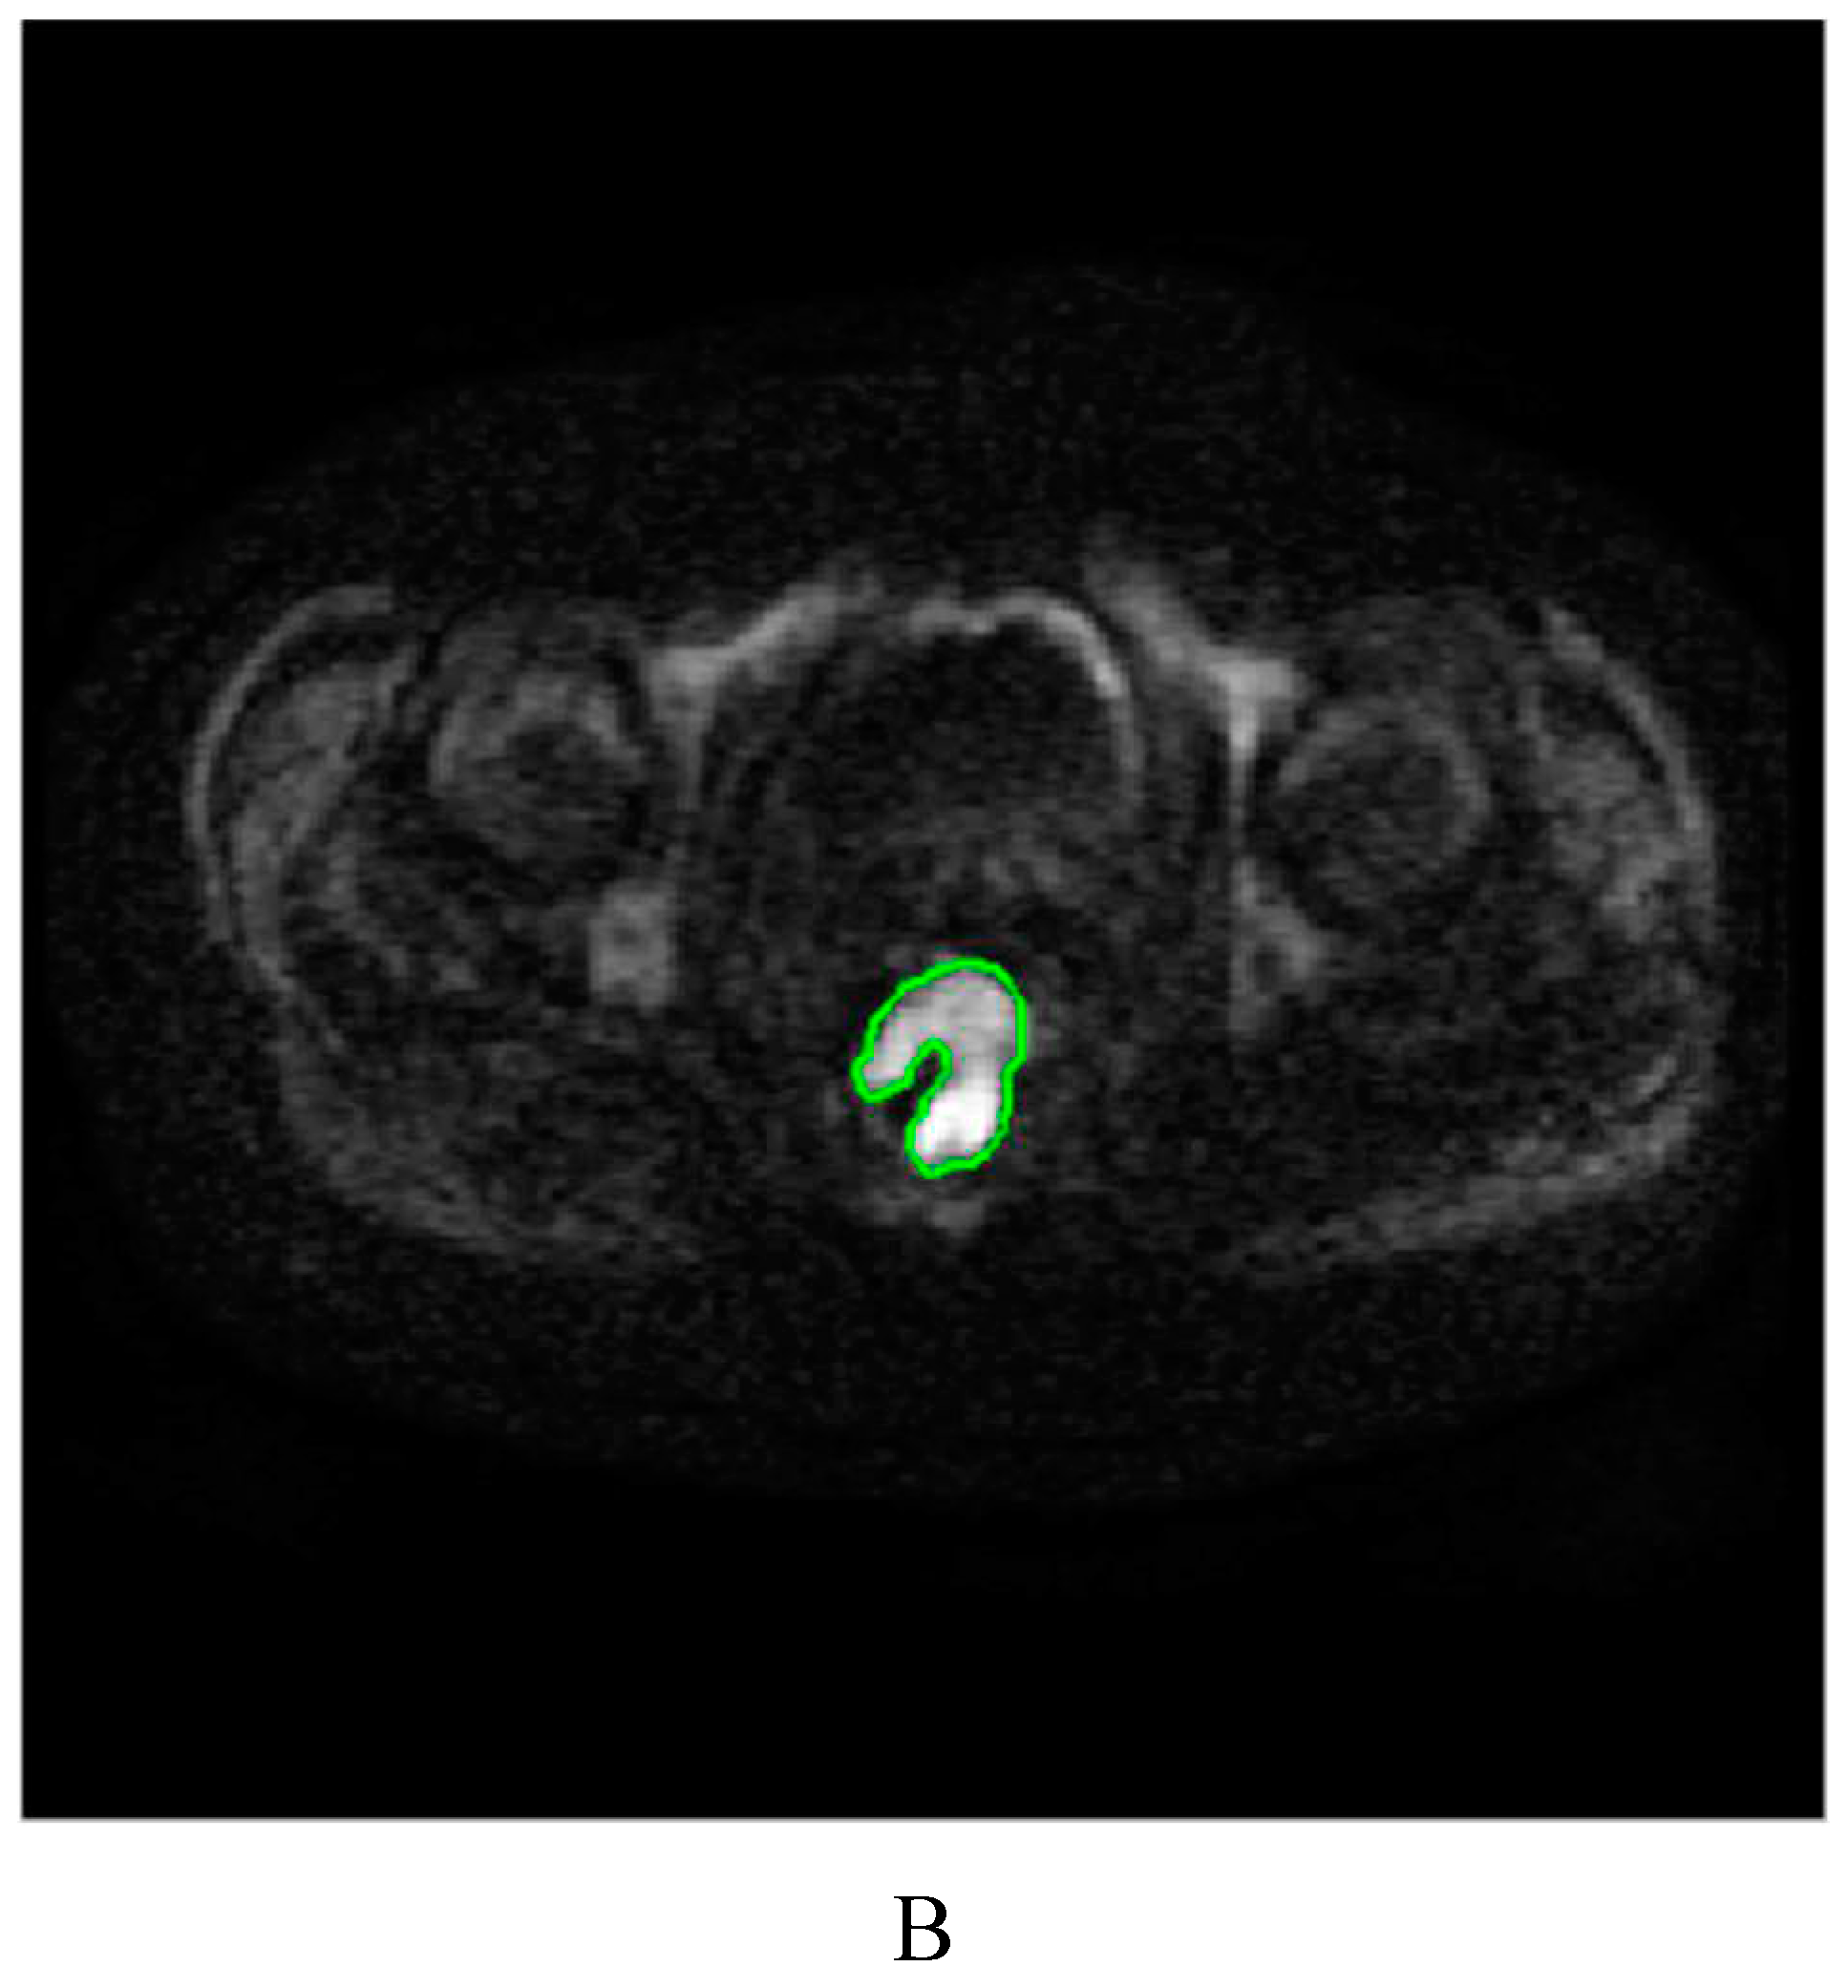

4.3. Image segmentation and feature extraction

| (oblique) axial DWI | 3000-7000/50-80 | 4-6 | 128-160×192 | 340-380×340–380 | 90 |